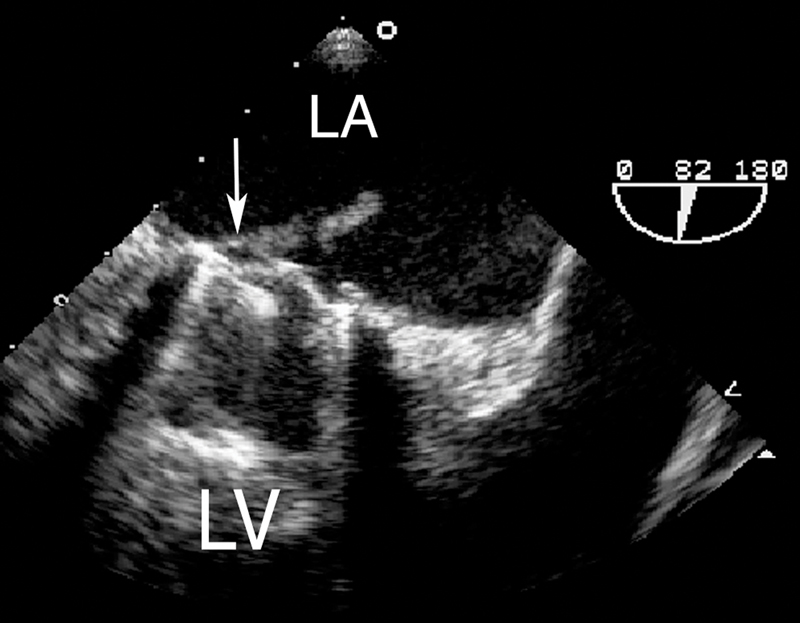

فحوصات تشخيصية لبعض امراض القلب والشرايين التاجية